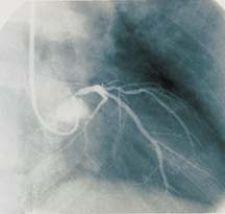

The system is FDA approved for use in children over one year of age and is approved for a broad range of diagnostic procedures requiring intravascular contrast, such as coronary angiography, CT, IVP and venography.